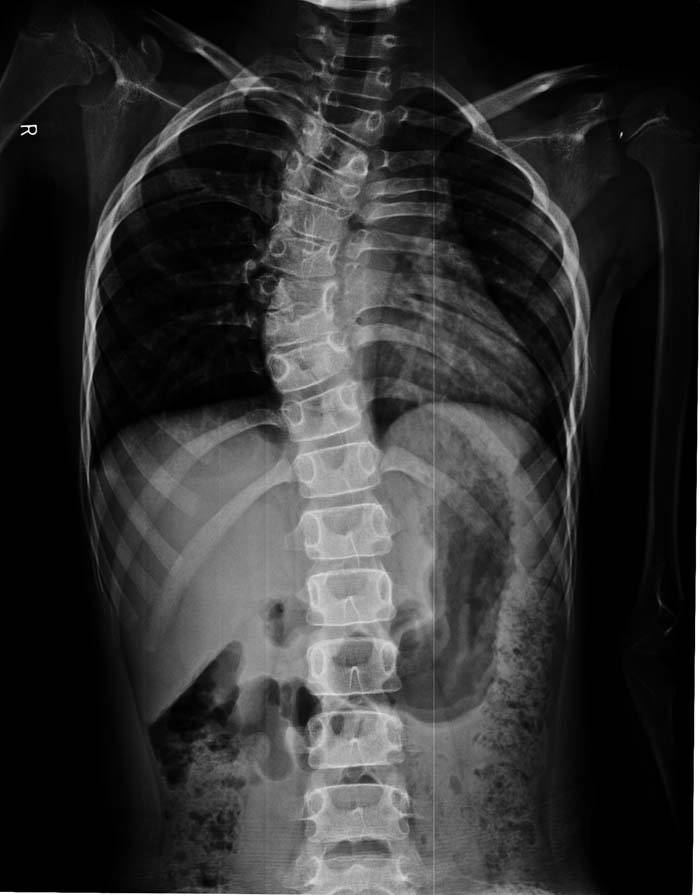

以下是引用zsl6918在2009-10-17 18:51:00的发言:[br]融椎畸形

以下是引用zy_zj在2009-10-17 19:21:00的发言:[br]胸椎8,9椎体融合畸形,伴序列s形弯曲,颈椎稍侧弯,曲度反向。

以下是引用余辉在2009-10-18 10:20:00的发言:[br]支持椎体隔合畸形,肋骨亦有融合,局部椎体密度较低,棘突影像缺如,不排除合并椎体裂,建议ct检查